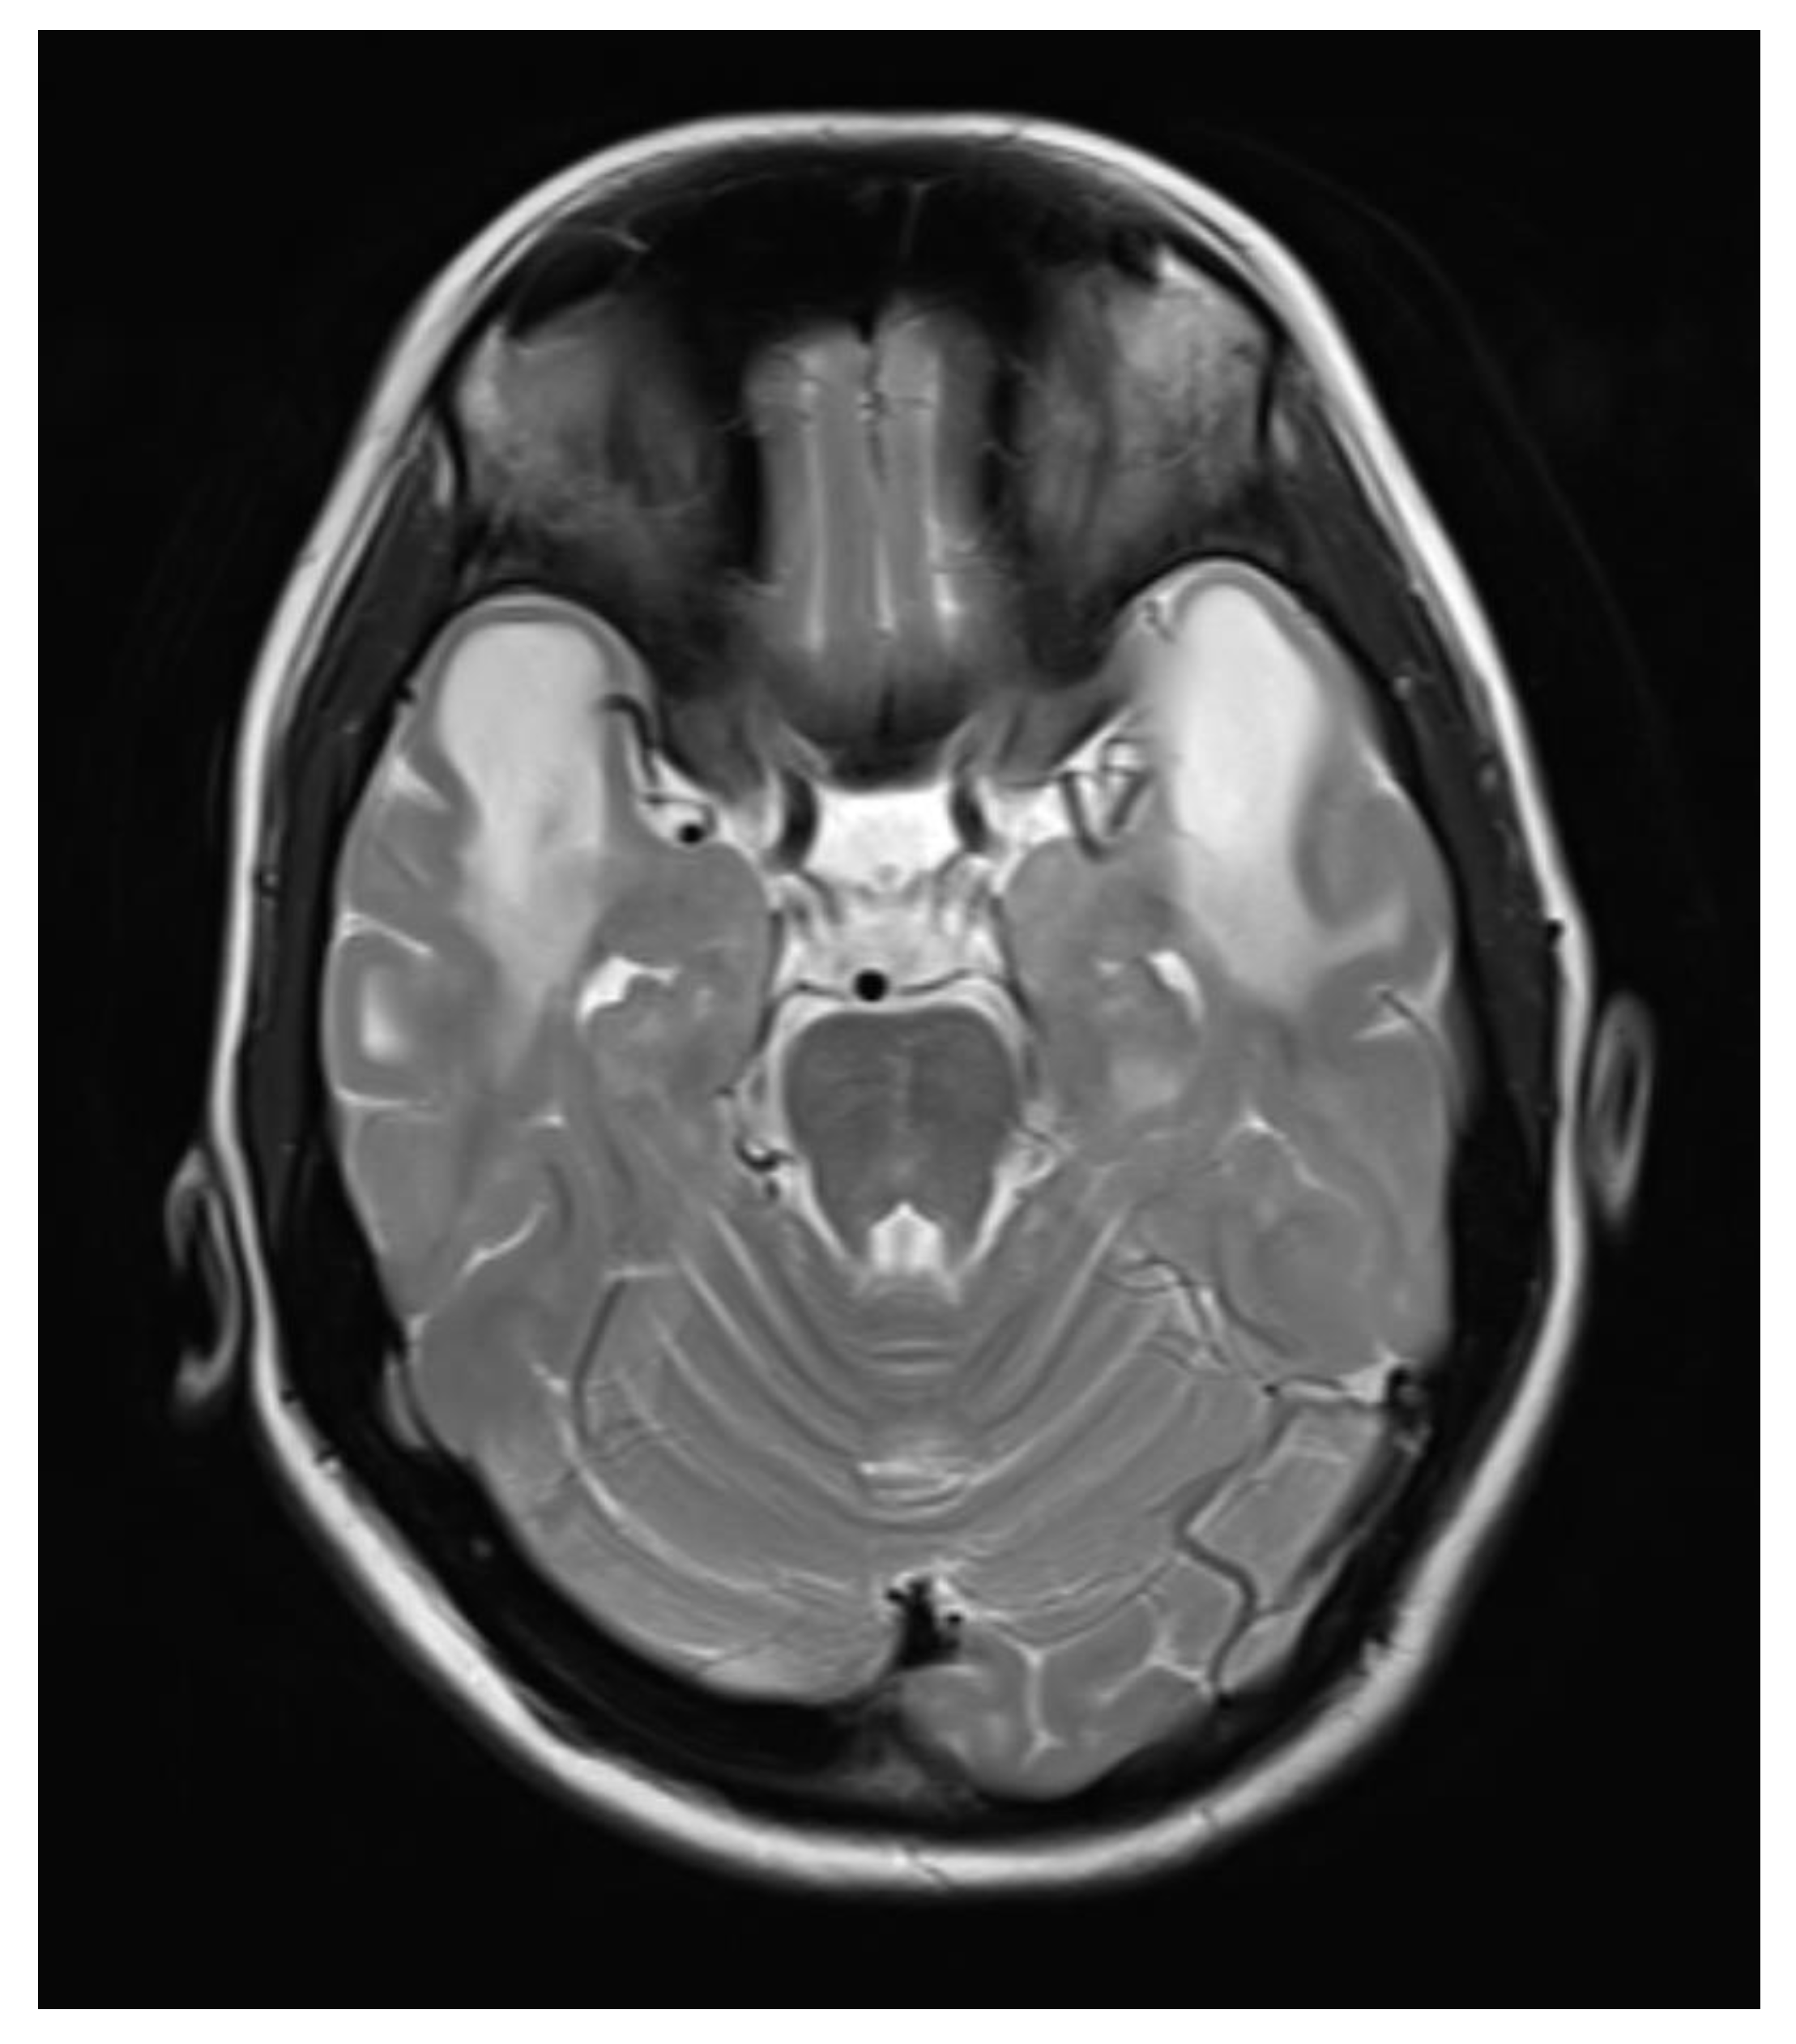

A contrast-enhanced MRI of the brain was performed, bilateral symmetrical diffuse abnormal T2WI/FLAIR hyperintensity involving the subcortical and periventricular deep white matter of bilateral cerebral hemispheres and corpus callosum with areas of diffuse restriction in bilateral centrum semi-ovale restriction, subcortical cysts, and cerebral atrophy were seen with possibility of Megalencephalic leukoencephalopathy with subcortical cysts also known as Van der knap disease. Post-contrast imaging showed normal enhancement, ruling out vascular abnormalities or abnormal enhancement patterns.

Figure 5. Axial T2WI images showing Subcortical and periventricular white matter hyperintensity with subcortical cyst formation in the bilateral anterior temporal lobe.

The clinical and radiological findings were consistent with megalencephalic leukoencephalopathy with subcortical cysts, also known as Van der Knaap disease.